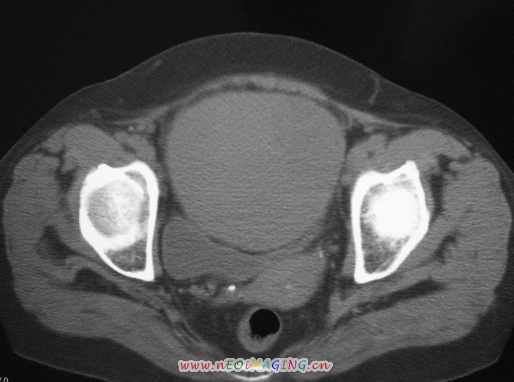

女56岁以右输尿管结石入院

病灶位于下腹部盆腔,从子宫与膀胱明显受压后移看,应该来源于盆腹腔的占位,病灶实性部分密度均匀,左侧可见低密度灶,建议增强扫描,考虑:间叶性肿瘤,或硬纤维瘤,输尿管下段结石伴上段输尿管扩张

右侧盆腔占位,考虑来源于卵巢,囊腺瘤可能性大。

右侧输尿管结石。

1)盆腔占位性病变,考虑来源于卵巢,囊腺瘤可能性大。2)右侧输尿管第二狭窄处结石伴梗阻。

今天病人已经手术证实为右附件囊肿,右侧输尿管第二狭窄处结石伴梗阻!!!

[病理诊断] CT11527:右附件囊肿,右侧输尿管结石。